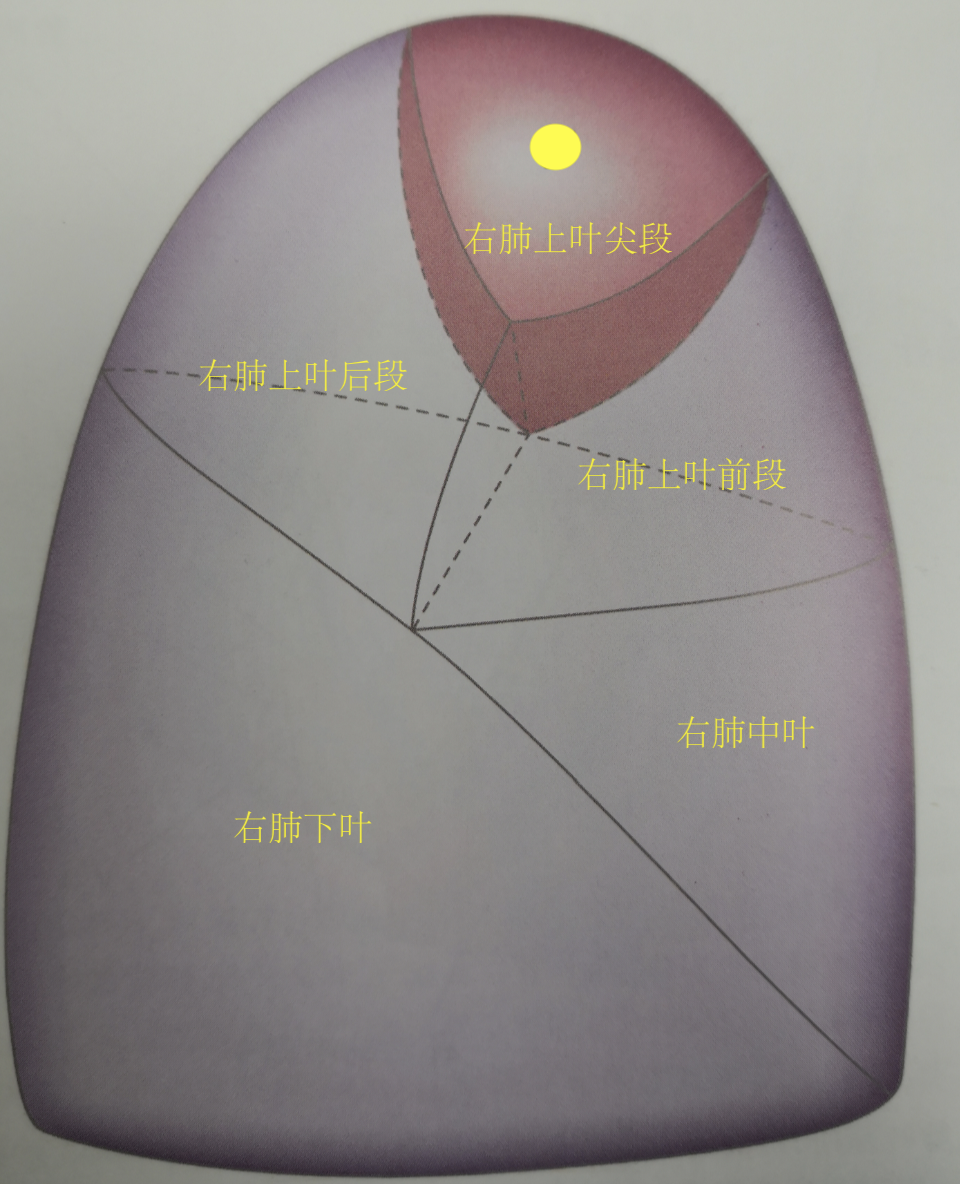

通过以上几点临床就基本可以判定这个结节是早期肺癌,至少微浸润以上,很可能已经达到了浸润,但因为已观察1年半无明显变化,判断侵袭性不高,所以我们为患者制定了胸腔镜右肺上叶尖段切除术,就是切除1个肺叶的1/3,既达到了根治性切除的目的,又最大限度的保留了肺功能。

小黄圈就是病灶位置,所在的深色区域是尖段,就是手术切除的部分